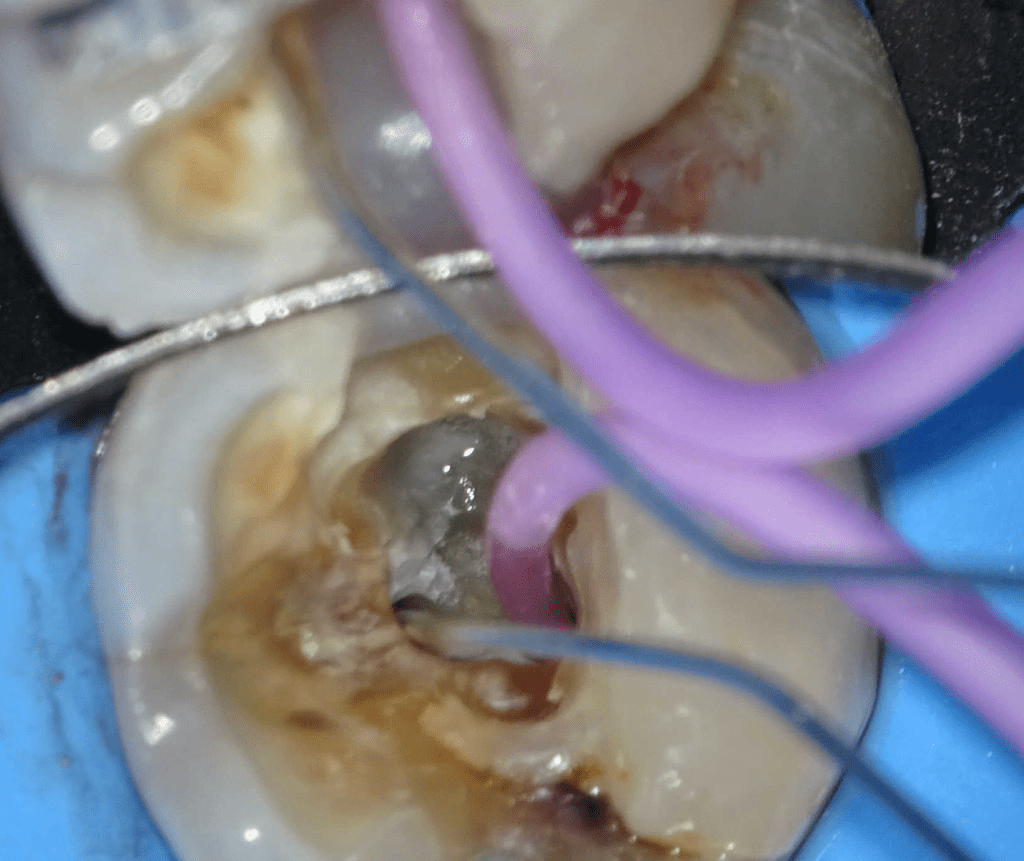

Pulpotomía biodentine + reco preendio